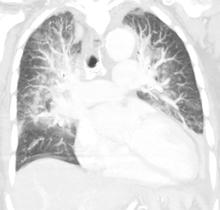

| Pulmonary edema with small pleural effusions on both sides. | |

Low oxygen saturation and disturbed arterial blood gas readings support the proposed diagnosis by suggesting a pulmonary shunt. Chest X-ray will show fluid in the alveolar walls, Kerley B lines, increased vascular shadowing in a classical batwing peri-hilum pattern, upper lobe diversion (increased blood flow to the superior parts of the lung), and possibly pleural effusions. In contrast, patchy alveolar infiltrates are more typically associated with noncardiogenic edema[2]